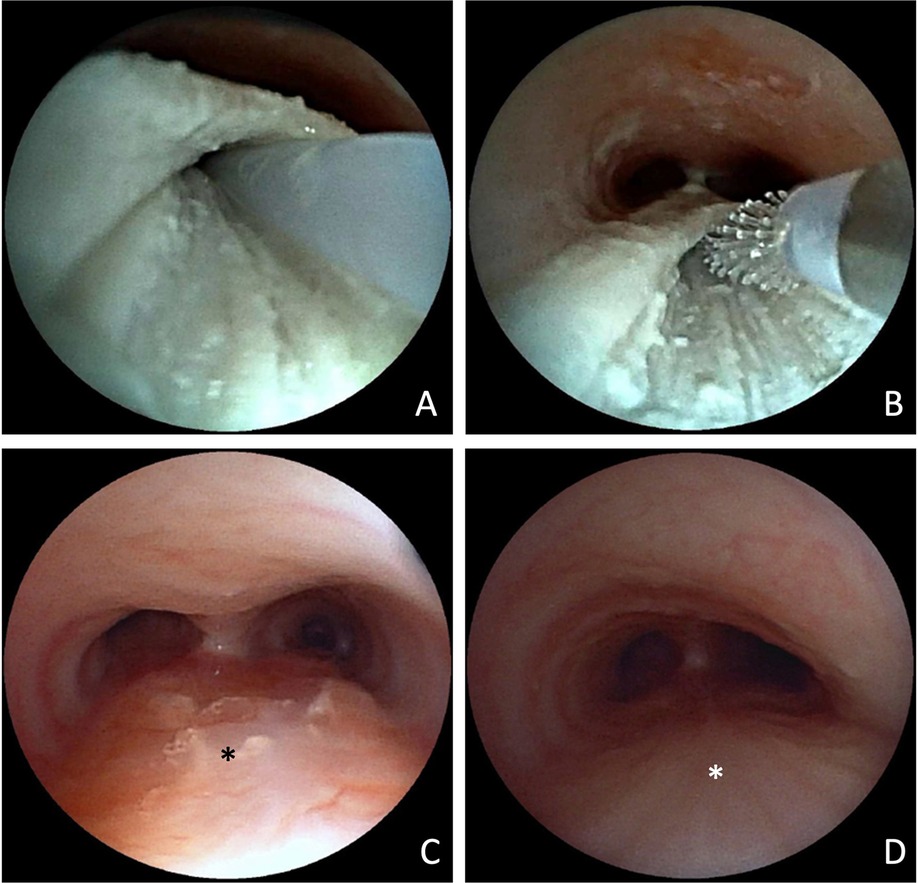

Two months after endoscopic removal of the migrated clip, follow-up bronchoscopy showed no evidence of a re-fistula. The former fistula pouch displayed a small ostium, which, however could not be probed, and no contrast medium passage into the mediastinum was observed even after direct application into the former fistula pouch. Despite this, the patient continued to experience food-associated coughing. At five months postoperatively, an esophageal barium swallow study was performed, revealing a recurrent TEF (Figure 3F). Subsequent bronchoscopy confirmed the diagnosis (Figures 3C–E). Endoscopic chemocauterization of the fistula was performed using a safety swab soaked in 50% trichloroacetic acid applied into the fistula pouch three times for 30s each, followed by fibrin glue application (Figure 4). Immediately the food-associated coughing resolved.

Figure 4. Bronchoscopic view of fistula pouch during chemocauterization with trichloroacetic acid. Application of fibrin glue (A) and mucosal abrasion via cytobrush (B). Bronchoscopic view of the trachea with former fistula pouch (*) 14 weeks (C) and 15 months after the procedure (D).